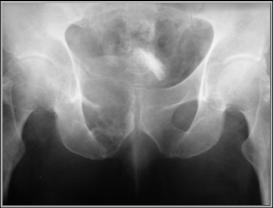

Chondrosarcoma